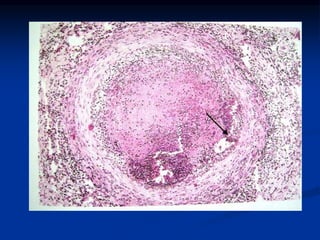

POLIARTERITIS NODOSA

Inflamación necrotizante transmural de las arteria musculares

de pequeño y mediano tamaño. Respeta la circulación

pulmonar.

Lesiones focales, aleatorias y episódicas

Producen dilataciones aneurismáticas, nódulos, obstrucción

vascular e infartos.

Enfermedad propia de adultos jóvenes.

Evolución aguda, subaguda y crónica. Largos intervalos

asintomáticos